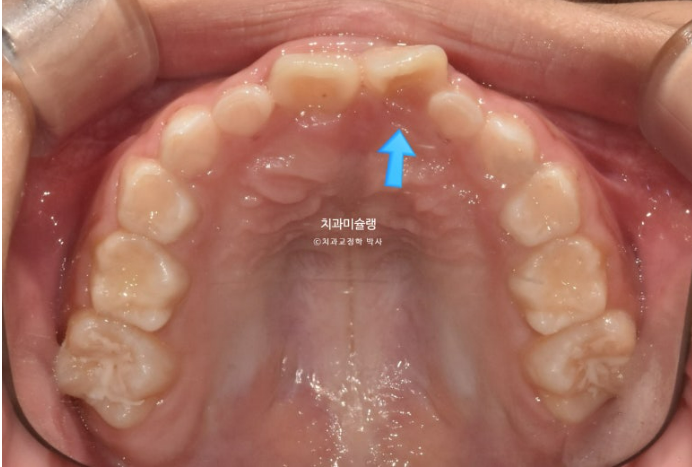

앞니가 거꾸로 물려서 온 7세 어린이 입니다.

윗니가 전체적으로 아랫니와 거꾸로 물리는 반대교합 입니다.

공간부족으로 앞니가 덧니처럼 나왔습니다.